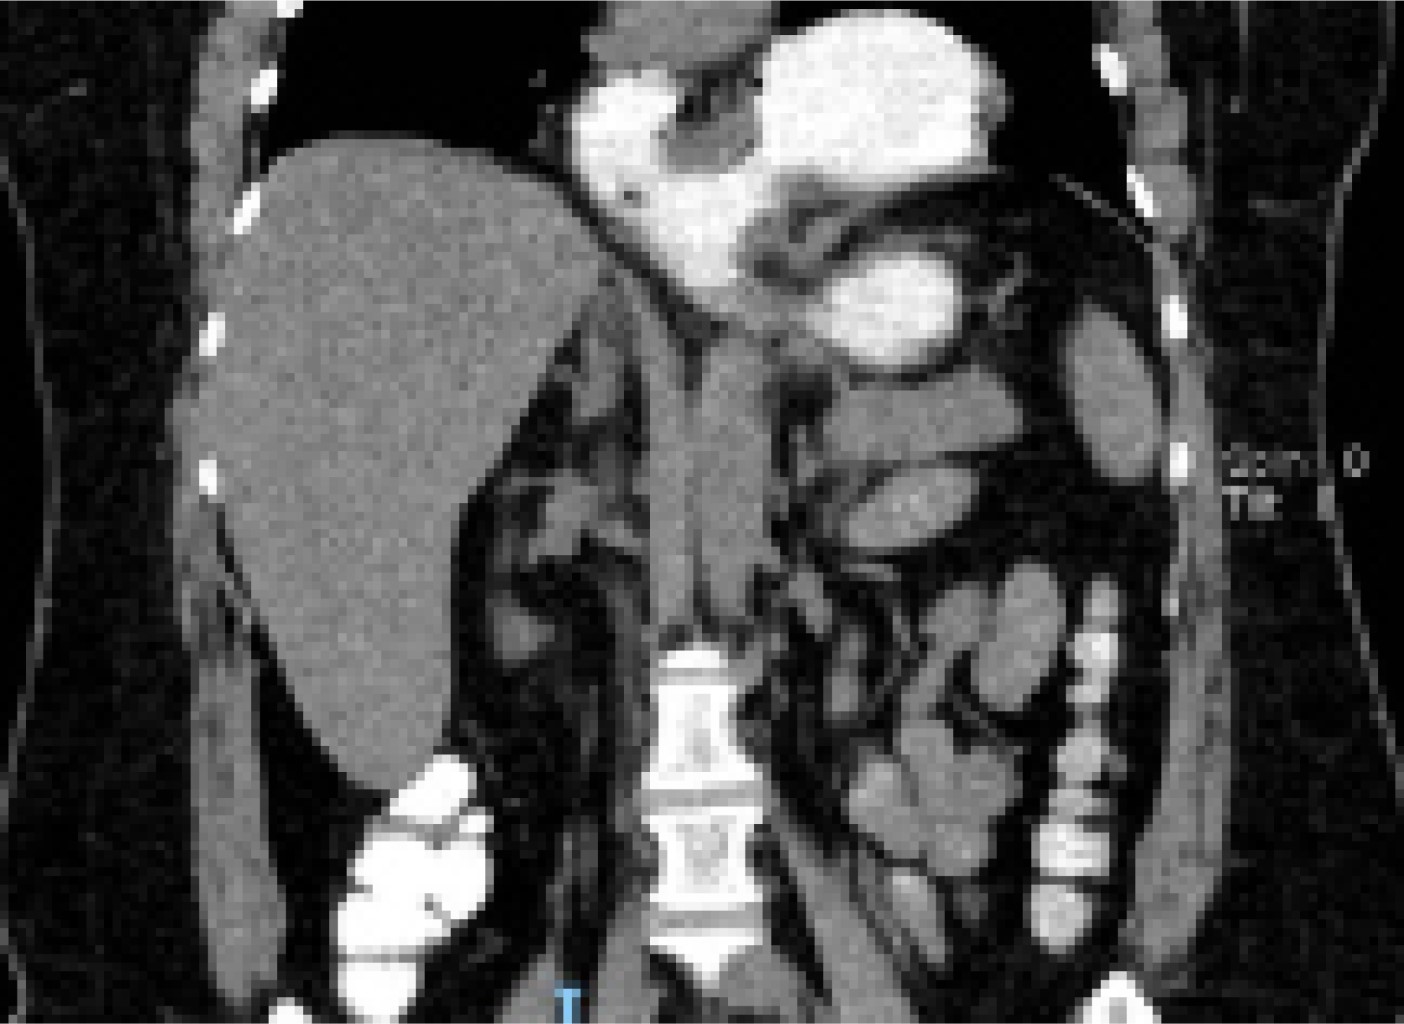

Los exámenes de laboratorio generales no mostraron alteraciones relevantes, pero ante la persistencia de dolor se solicitó tomografía axial computarizada (TAC) contrastada (Figura 1), que mostró evidencia de hernia hiatal mixta (por deslizamiento y paraesofágica) que desplazaba la silueta cardiaca y condicionaba atelectasias pasivas secundarias del parénquima de los segmentos basales adyacentes.

El VG es una condición poco frecuente que se define como rotación anormal del estómago mayor de 180o sobre su propio eje,1 inicialmente fue descrito por Berti en 1866.2 El diagnóstico temprano es de principal importancia debido al alto riesgo de morbimortalidad por las complicaciones potenciales que puede presentar, suele requerir tratamiento quirúrgico urgente.3 El cuadro clínico se caracteriza por la tríada de Borchardt: dolor epigástrico súbito con distensión abdominal, náusea sin vómito e incapacidad de introducir de forma correcta la sonda nasogástrica.4 En la radiografía simple de abdomen se observa el estómago distendido con niveles hidroaéreos y diafragma elevado. En la actualidad una tomografía computarizada es el estudio con mayor sensibilidad y especificidad, ya que es útil para identificar posición de píloro y cardias, determinar el tipo de VG según su eje de torsión y la relación que existe entre las curvaturas.5

Existen distintos tipos de VG, la clasificación utilizada es la de Singleton (Tabla 1). El diagnóstico suele ser difícil por la poca sospecha clínica, puede ir desde un hallazgo radiológico incidental hasta situaciones urgentes. En el examen con rayos X se puede detectar la dilatación gástrica con escasez de gas en la parte restante del intestino. Si el VG es en la forma mesentérico axial la sombra gástrica muestra doble nivel de aire y fluido en bipedestación, mientras que, en el órgano axial, el estómago se coloca más horizontal con un nivel de fluido único. La serie gastrointestinal superior se considera más específica que la radiografía, pues revela obstrucción del estómago en el sitio del vólvulo y su distensión a nivel del diafragma.4,10 En este caso la presentación clínica no fue clásica, ya que la paciente presentaba arcadas con vómito de contenido gástrico, por lo que se solicitó una TAC con contraste vía oral que confirmó el diagnóstico y la condición asociada de hernia paraesofágica.